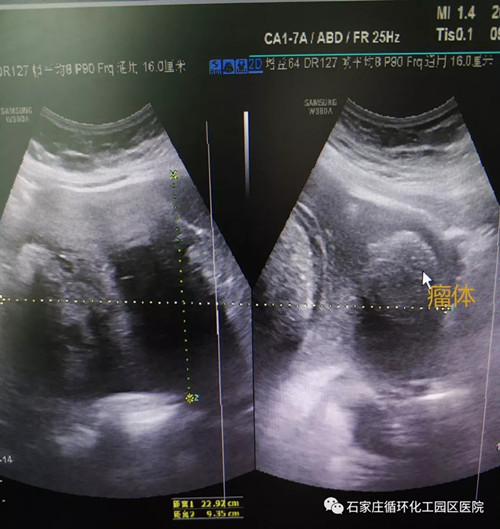

7月9日,園區(qū)醫(yī)院婦產(chǎn)科迎來(lái)了一位小腹不適的47歲女性,她的檢查結(jié)果令醫(yī)務(wù)人員震驚。盆腔彩超檢查發(fā)現(xiàn)附件囊實(shí)性較大包塊,CT檢查顯示下腹部有較大腫塊。一個(gè)22.9公分的巨大卵巢畸胎瘤安穩(wěn)地躺在患者的腹盆腔內(nèi),嚴(yán)重吞噬著患者的健康。

盆腔彩超影像